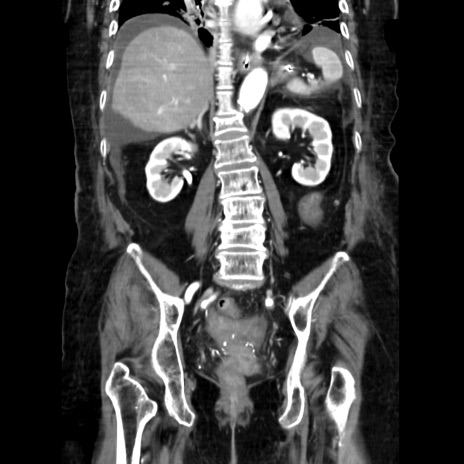

症例40(冠状断像)

【症例】90歳代女性

【主訴】腹痛・嘔吐

【現病歴】 食欲低下、嘔吐があり昨日他院受診。肺炎と診断され入院となる。入院後より腹部全体に圧痛あり。胃管留置され経過みていたが、症状持続するため、

当院転院となる。

【既往歴】胸椎圧迫骨折、胆石症

【身体所見】腹部:中央に激痛あり、圧痛あり、反跳痛不明

【データ】WBC 17100、CRP 18.82

冠状断像